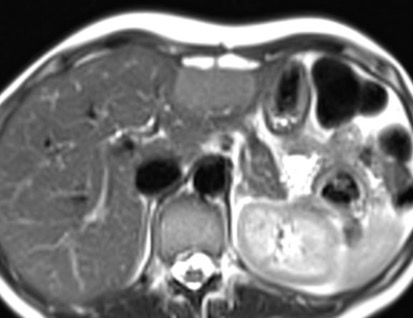

Aspetto RM

- Alterazione focale ben circoscritta, ipointensa in T1, iperintensa in T2 (isointensa al liquor), priva di enhancement post-contrastografico.

- Nelle sequenze colangiografiche non si riconosce una comunicazione con l’albero biliare.

- La cisti epatica a contenuto proteinaceo ha segnale iperintenso in T1.

- Nel caso di emorragia intracistica, il segnale sarà eterogeneo sia nelle sequenze T1 che T2, spesso con un livello fluido-fluido.